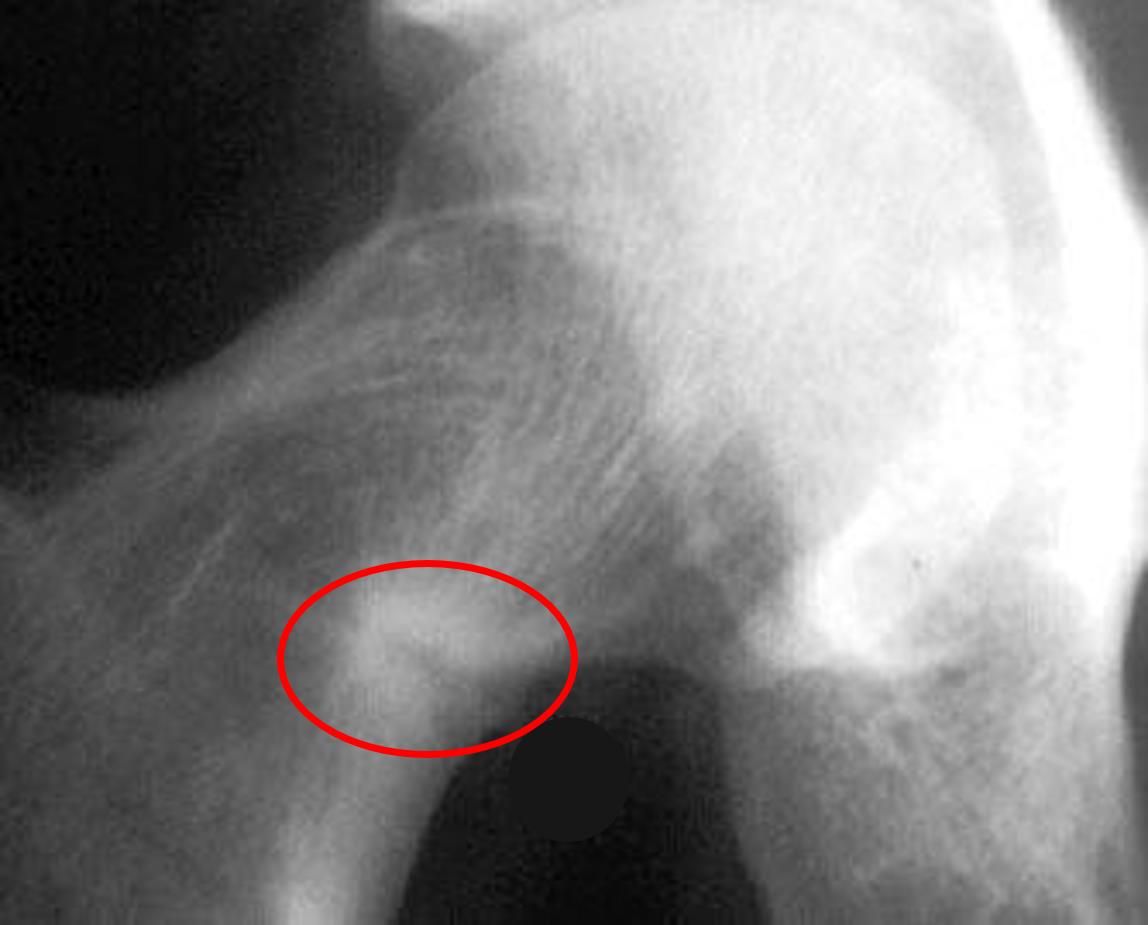

A radiograph is shown in Figure A. Which of the following is the most likely cause of this patient's symptoms?

Figure/Illustration A is a radiograph demonstrating lucency in the inferior aspect of the femoral neck (red circle). These findings are known as Looser lines and are consistent with renal osteodystrophy.